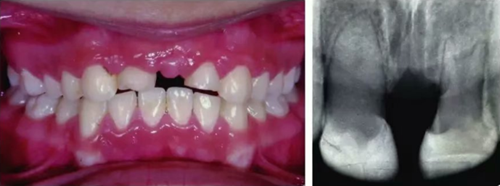

初步正畸牽引嵌入的上頜側(cè)切牙并重新獲得切牙空間。上頜側(cè)切牙的預(yù)后顯示有嚴(yán)重的牙根吸收。因此需要拔除上頜側(cè)切牙(圖3)。

圖3. 影像學(xué)顯示上頜側(cè)切牙牙根吸收

6個(gè)月后,移植牙的根尖片顯示治療期間沒(méi)有出現(xiàn)牙根吸收的影像。患者沒(méi)有出現(xiàn)不適,沒(méi)有發(fā)生牙齦炎。在23個(gè)月期間沒(méi)有進(jìn)行任何修復(fù)完成治療,達(dá)到I類關(guān)系(圖5和圖6)。

圖5. 正畸后影像學(xué)檢查

圖6. 正畸后口內(nèi)照